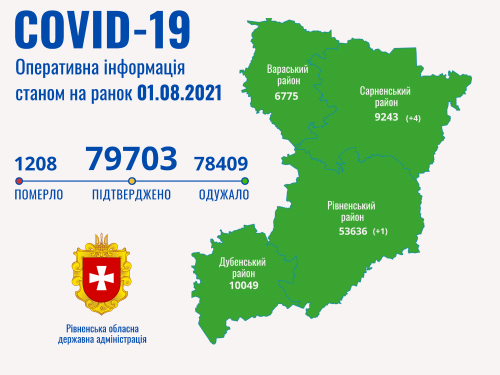

Коронавірус повертається: як стрімко зростає кількість хворих на Рівненщині (ВІДЕО)

Пів тисячі - у важкому стані, 9 жителів Рівненщини померли за добу від коронавірусу